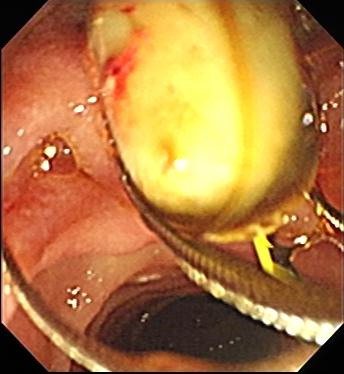

ERCP即逆行胰胆管造影术,是内镜中操作难度最大的技术之一,医生只用1厘米粗的内镜就能完成取胆管结石、放支架、切肿瘤、疏通胆道及胰管等复杂手术治疗胆石病、胰腺炎、胆管炎、胰管结石及恶性肿瘤引起的梗阻性黄疸,是“无切口治疗胆胰疾病”的主要手段。

本次活动共演示了十二指肠乳头切开术、十二指肠乳头水囊扩张术、胆总管取石术、胰管支架置放术、胰管支架取出术、鼻胆管引流术、胆管金属支架置入术等无切口治疗胆结石、急性化脓性胆管炎、胰腺炎、梗阻性黄疸等等胆胰外科疾病,就术中遇见的憩室内乳头、困难插管、乳头位置变异、水囊扩张注意的问题、网篮取石的技巧进行了探讨,对ERCP的并发症的发生、预防和治疗等进行了重点讲解,分享了经验。